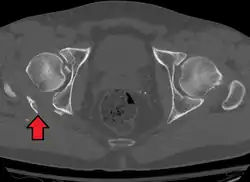

-

Axial CT image (viewed on bone windows) of a complex comminuted left acetabular fracture involving both anterior and posterior columns. -